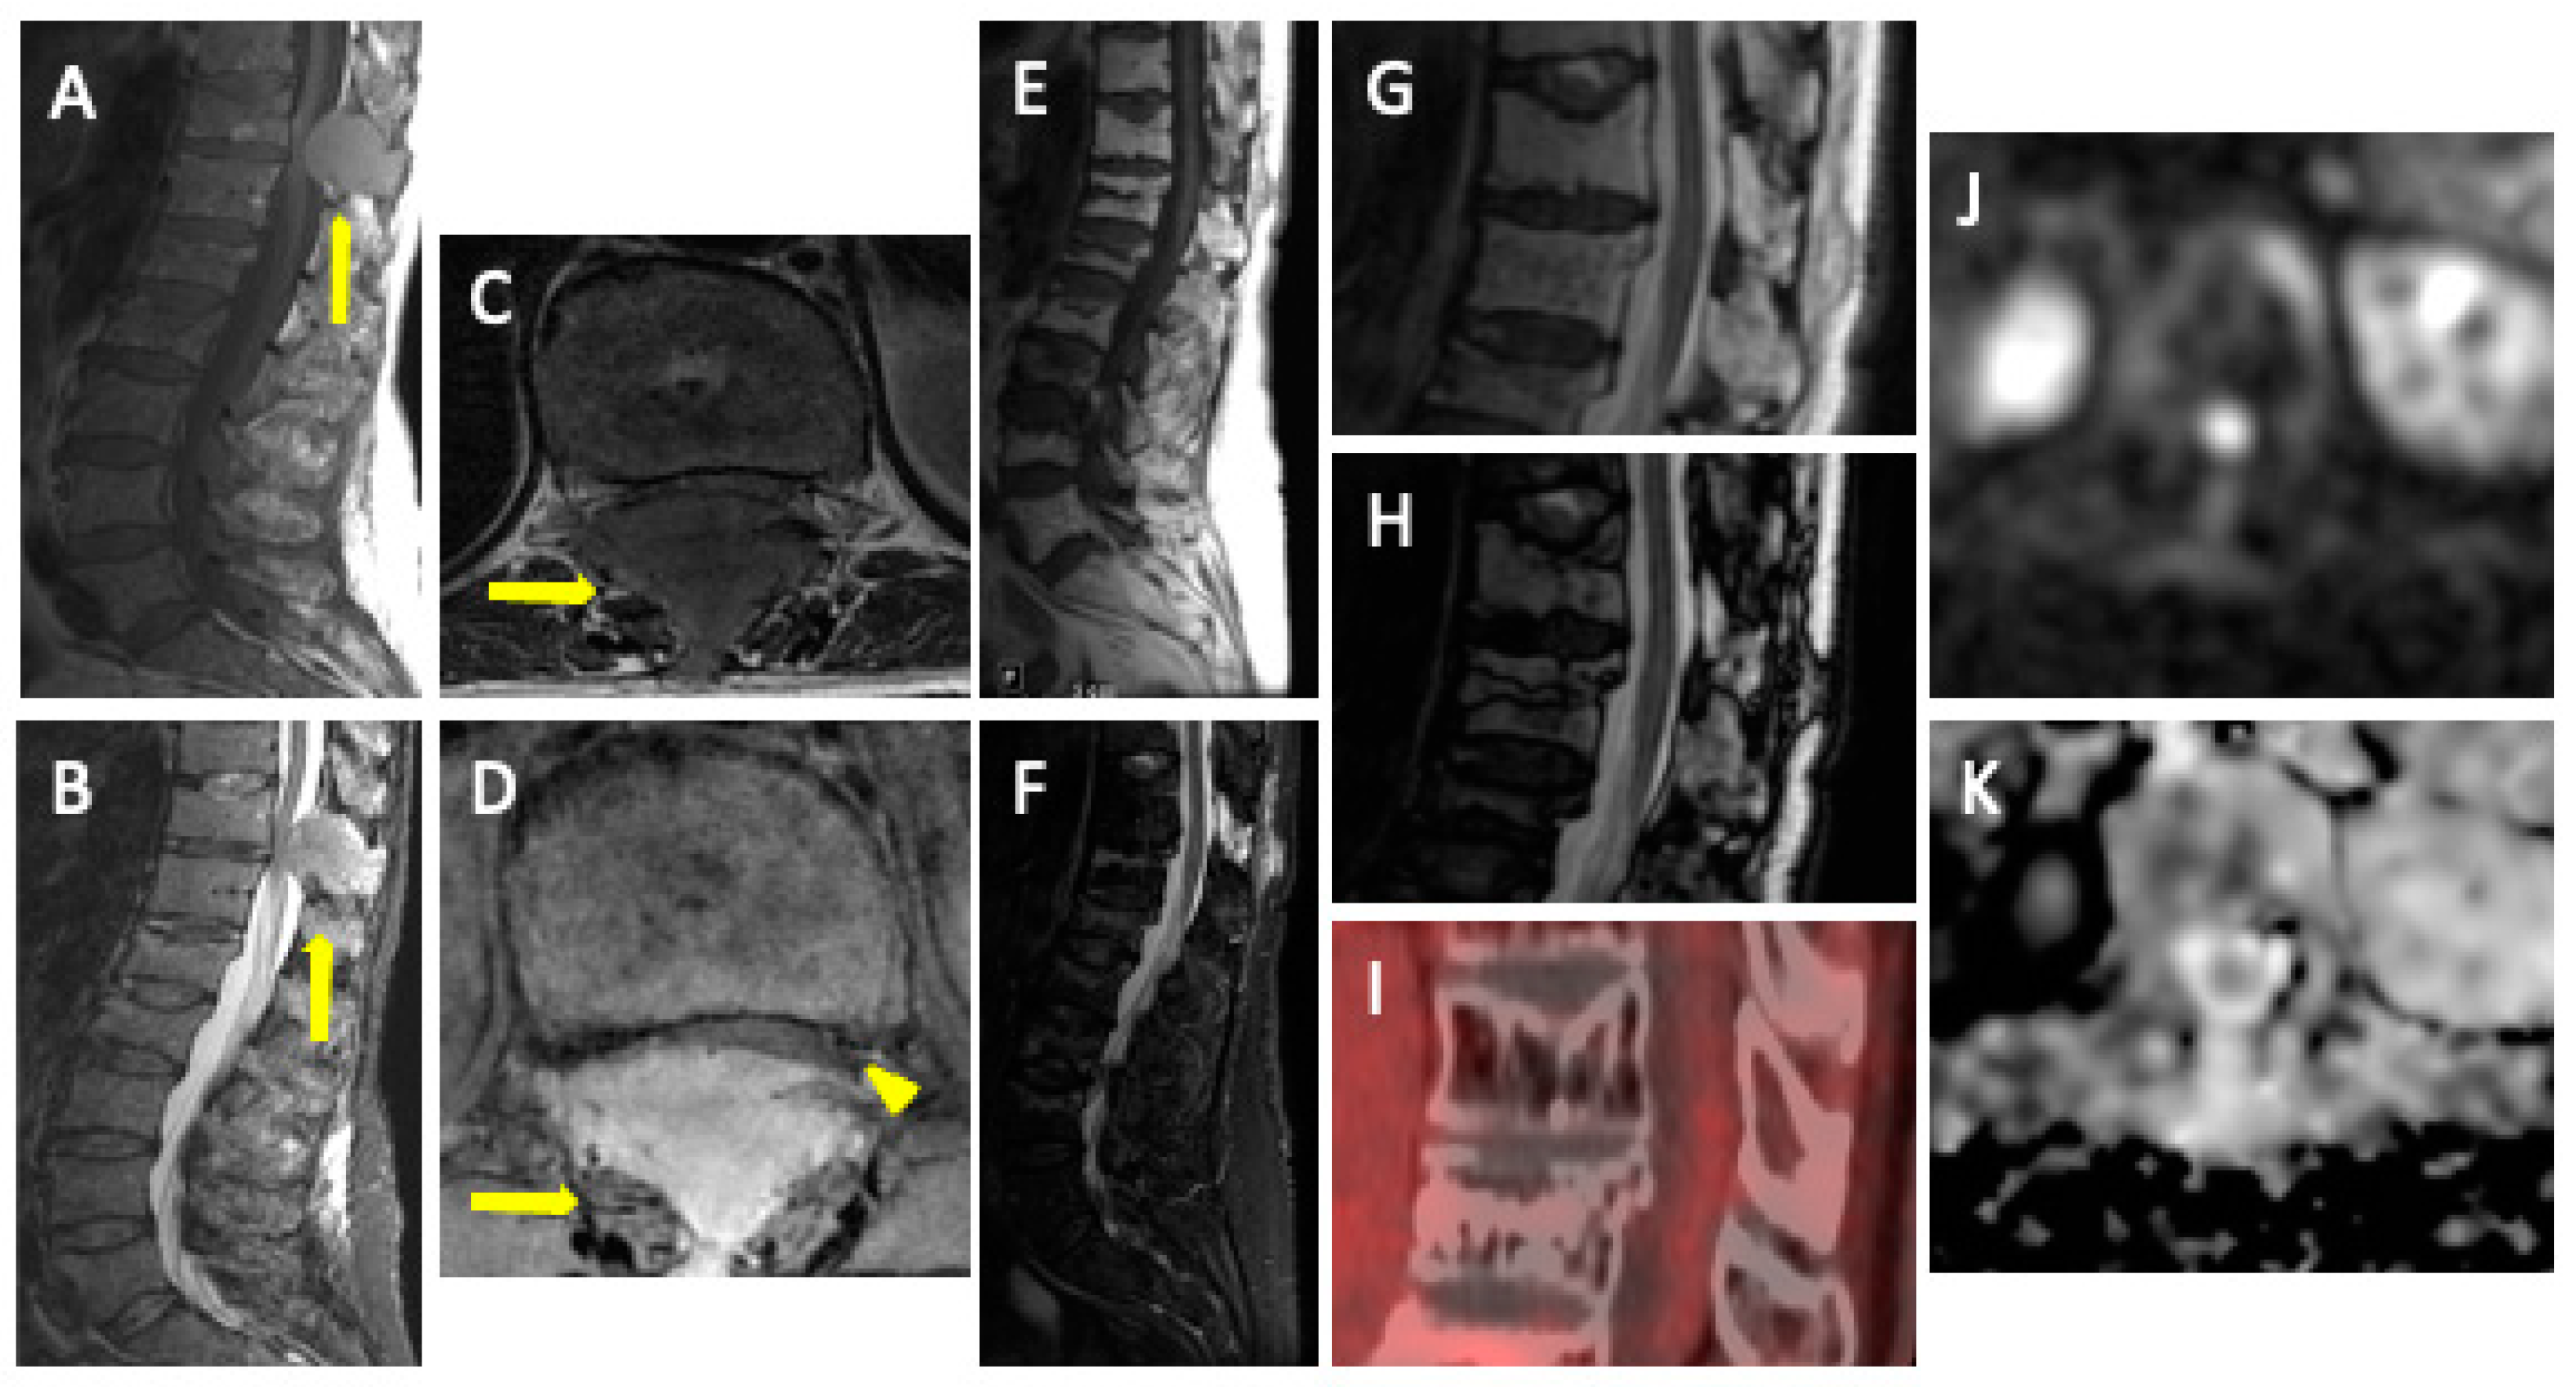

- Diffuse pattern: Diffuse disease can be suspected from a diffuse decreased signal on T1WI (either iso- or hypointense to intervertebral discs and muscle) and a diffuse increased signal throughout the marrow on T2FSWI, STIR, or high b-value DWI. Marrow ADC values above 600–700 μm2/s in a nontreated and newly diagnosed patient with MM could be used to increase confidence for the diagnosis of diffuse marrow involvement [33] (Figure 7). Due to potential false-positive findings, diffuse disease in imaging must be supported by bone marrow trephine biopsy [26].